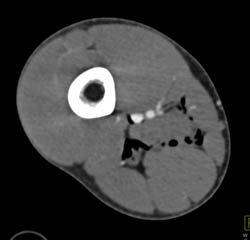

Cellulitis on CTA